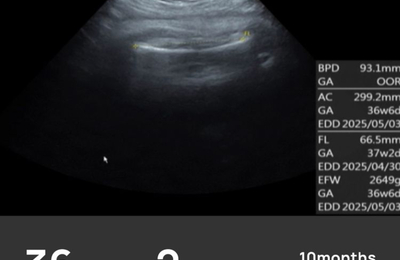

ついに妊娠36週、臨月に入りました。 出産予定日まであと1ヶ月を切り、いよいよ本番が近づいてきた…そんな気持ちが強くなってきました。 赤ちゃんの成長記録(36週) BPD(頭の横幅):93.1mm AC(お腹周り):299.2mm FL(太ももの骨の長さ):66.5mm EFW(推定体重):2649g 赤ちゃんはすでに2600gを超える大きさに! もういつ産まれてきてもおかしくないくらいに育ってき…